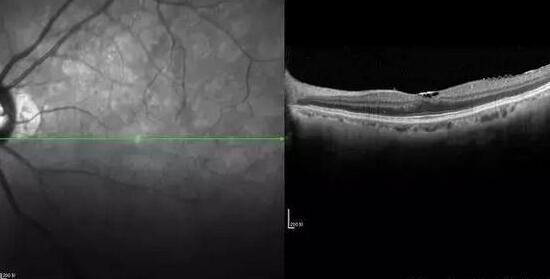

黄斑前膜